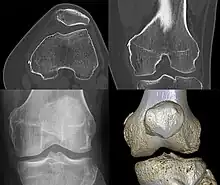

Diagnosis is typically made on radiographs demonstrating the Pellegrini-Stieda syndrome sign accompanied by pain or restriction of range-of-motion of the knee joint.[2] Pellegrini-Stieda syndrome sign is typically described by a longitudinally linear opacity, which is a process that is describes characteristic of calcification in the soft tissue located medial to the medial femoral condyle.[2] This calcification seen on imaging represents the ossification of the medial collateral ligament, which typically does not develop until approximately three weeks after the initial injury.[2]It is important to note to distinguish this radiographic finding from that of a medial femoral condyle avulsion fracture, which is an injury in which a pulling force of a tendon or ligament fractures away a piece of the bone from its attachment site.[2]

Alternative classification syndrome for Pellegrini-Stieda lesions of Type 1 through Type 4 based on their location:[2]

- Type 1- is referred to as a beak-like appearance and describes the ossification arising from the femur and extending inferiorly in the medial collateral ligament.

- Type 2-is defines a tear-drop pattern, localized within the medial collateral ligament without any attachment to the femur.

- Type 3-presents as an elongated ossification superior to the femur lying in the distal adductor magnus tendon.

- Type 4-is also characterized as a beak-like appearance arising from the femur. However, there are some cases where this ossification extends into both the medial collateral ligament and adductor magnus tendon. In then, the original attribution of the syndrome to the medial collateral ligament may now be outdated as many publications have suggested concomitant and even sometimes preferential involvement of the adductor magnus tendon, medial head of the gastrocnemius, or medial patellofemoral ligament.[2]